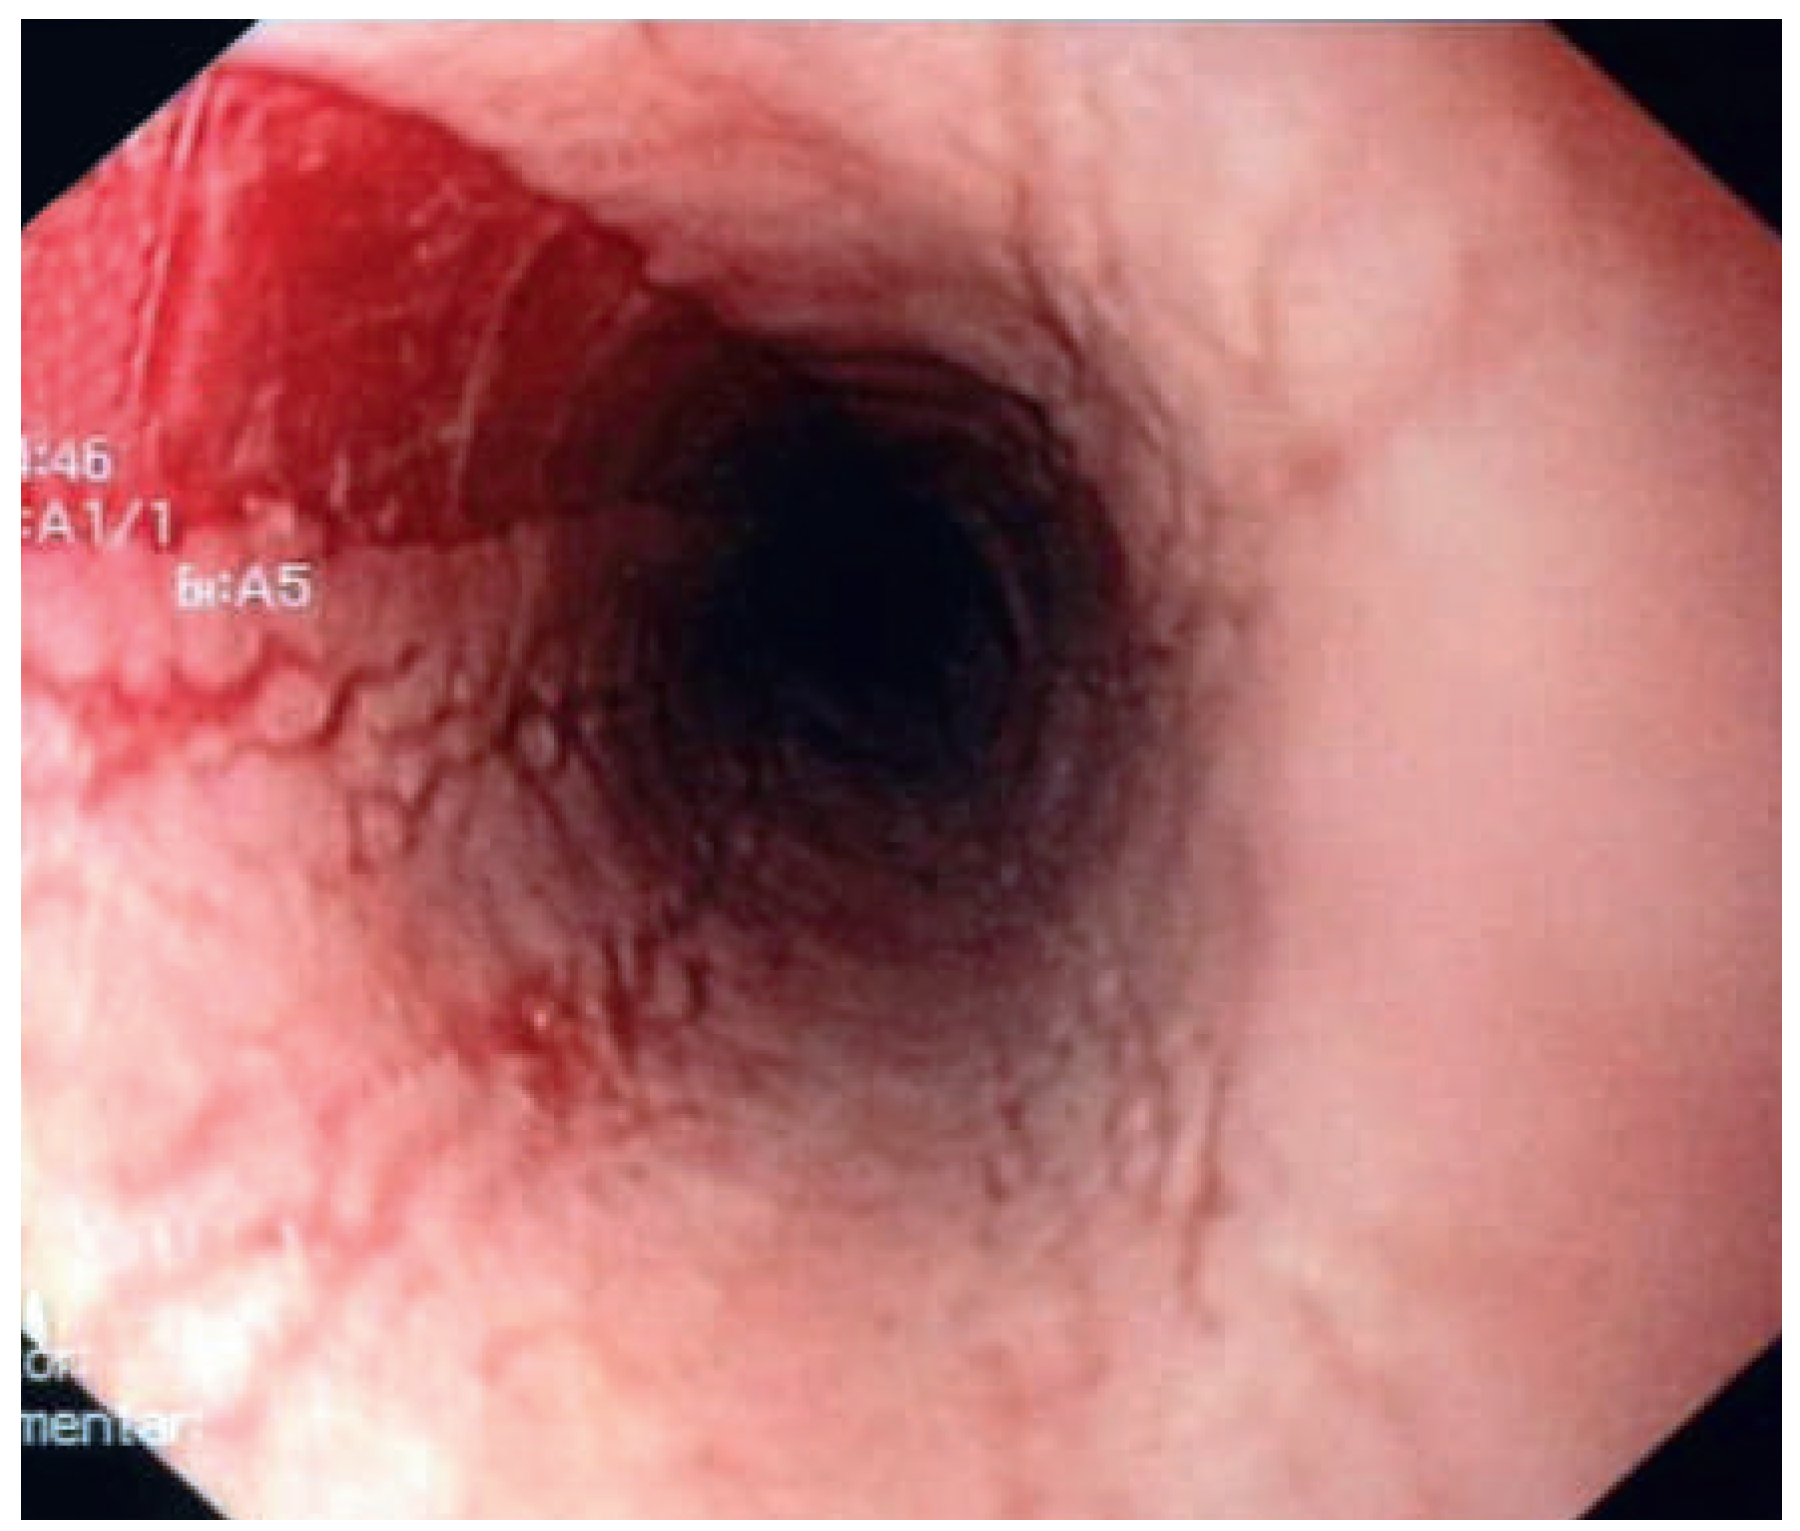

Die akute Bolusobstruktion ist eine typische Erstmanifestation, welche eine notfallmässige endoskopische Behandlung erfordert. Andere Betroffene leiden über Jahre hinweg an einer unterschiedlich ausgeprägten, zeitlich fluktuierenden Dysphagie, bevor die Diagnose mittels Ösophagoskopie und Biopsie gestellt wird. Die Behandlung besteht in der Regel in einer topischen Steroidtherapie. Der Krankheitsverlauf ist chronisch. Ein substantieller Anteil der Patienten erleidet eine Progression in Form eines Elastizitätsverlusts der Speiseröhre (sog. «Remodelling»). Daraus können längerstreckige Stenosen resultieren, die zwar anfänglich nur mässiggradig ausgeprägt sind, trotzdem aber schon eine markante Rigidität und Brüchigkeit des Gewebes aufweisen. Schon die vorsichtige diagnostische Endoskopie kann zu erheblichen Verletzungen führen (Abb. 6). Somit muss die TEE-Komplikationsgefahr als erhöht eingestuft werden. Patienten mit Verdacht auf (oder nachgewiesener) eosinophiler Ösophagitis sollten vor einer TEE endoskopiert werden, um die Frage von Stenosen zu klären.

Abbildung 6. Einriss der Ösophagusmukosa infolge diagnostischerflexibler Ösophagoskopie bei Elastizitätsverlust bei Eosinophiler Ösophagitis.